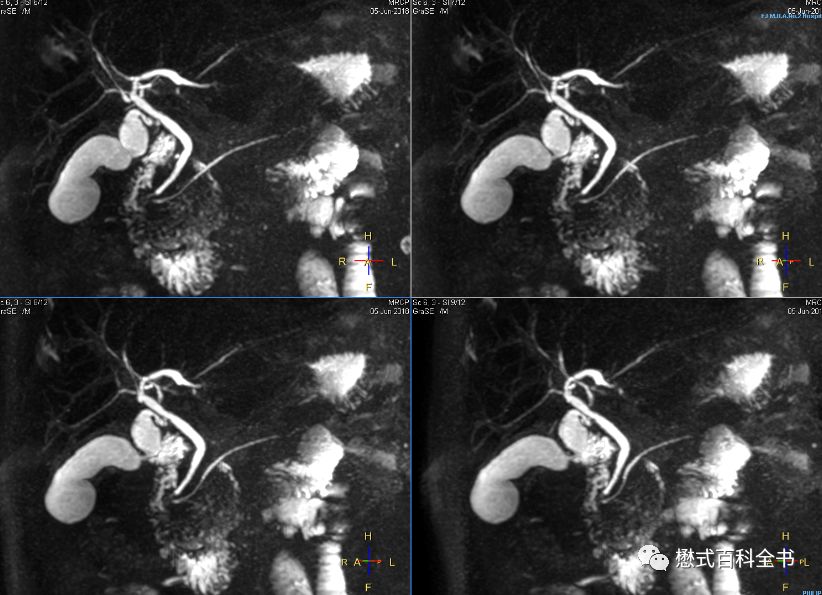

图14~16:扫描MRCP前注射6-542,十二指肠蠕动得到有效抑制,胆总管下段及十二指肠乳头部显示清楚(图片来源于陕西省汉中市中心医院培训)